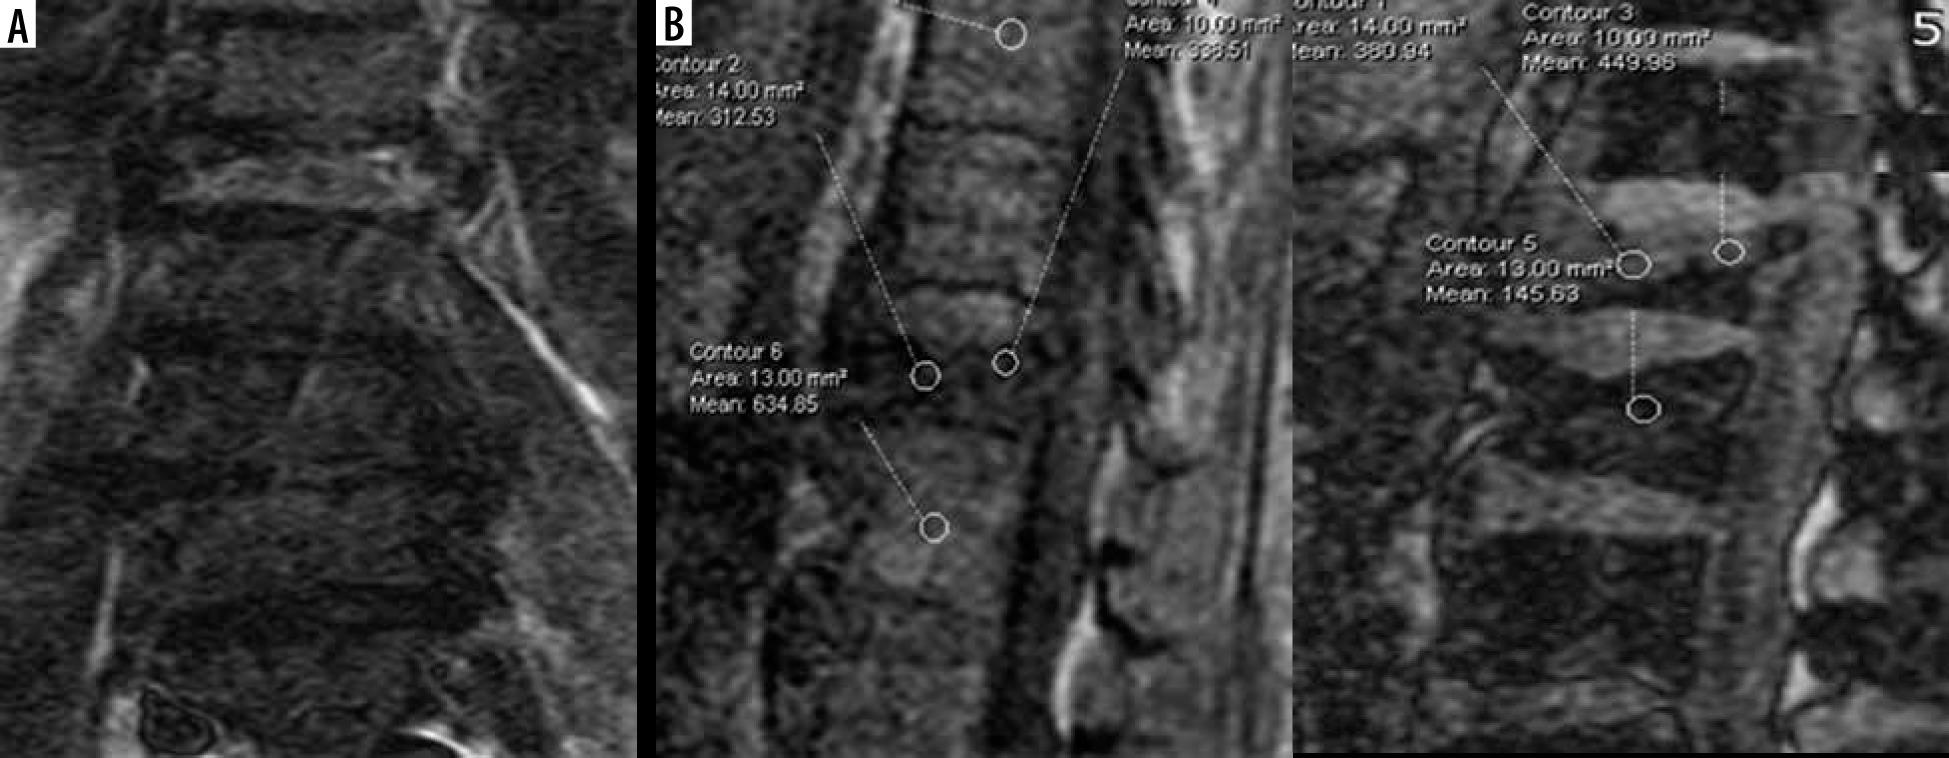

The mean signal intensity ratio (SIR) value of malignant lesions on CSI was 0.967 (Figures 4 and 5), and of benign lesions it was 0.76 (Figures 6 and 7). Using ROC analysis, SIR cut-off value of 0.96 was defined in our study to differentiate between benign osteoporotic and malignant vertebral marrow lesions. The area under the curve came was 0.758 and the p-value was 0.006.

Figure 4

A) Coronal STIR images showing STIR hyperintensity at D9 vertebra. B) Sagittal chemical shift imaging (CSI) showing CSI in-phase and out-of-phase images of the same lesion in which signal intensity ratio was 1.17

Figure 5

A) Sagittal STIR image-showing STIR hyperintensity and collapsed vertebra at D11 level. B) Sagittal chemical shift imaging (CSI) showing CSI in-phase and out-of-phase images of the same lesion in which signal intensity ratio was 1.02